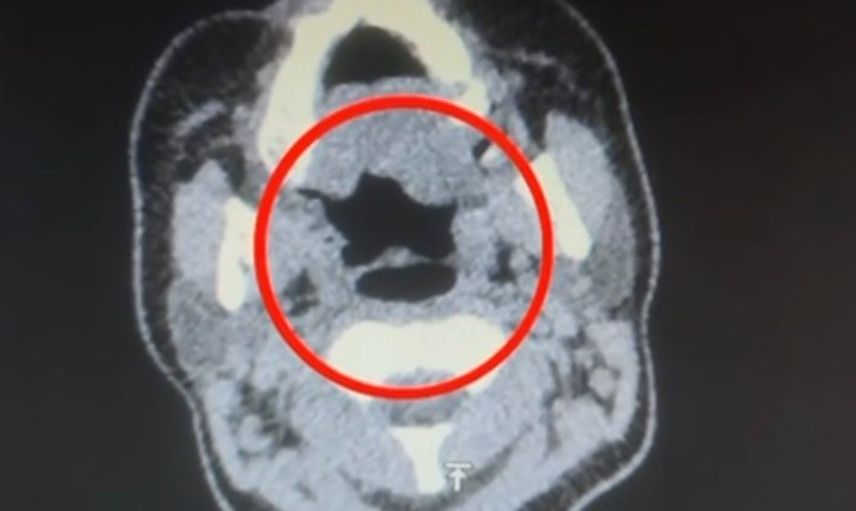

Şüpheli, hastaneye götürülerek iç beden muayenesine tabi tutuldu. Yapılan muayenede, şüphelinin midesinde 50 adet kapsül şeklinde toplamda 500 gram uyuşturucu madde bulunduğu tespit edildi.